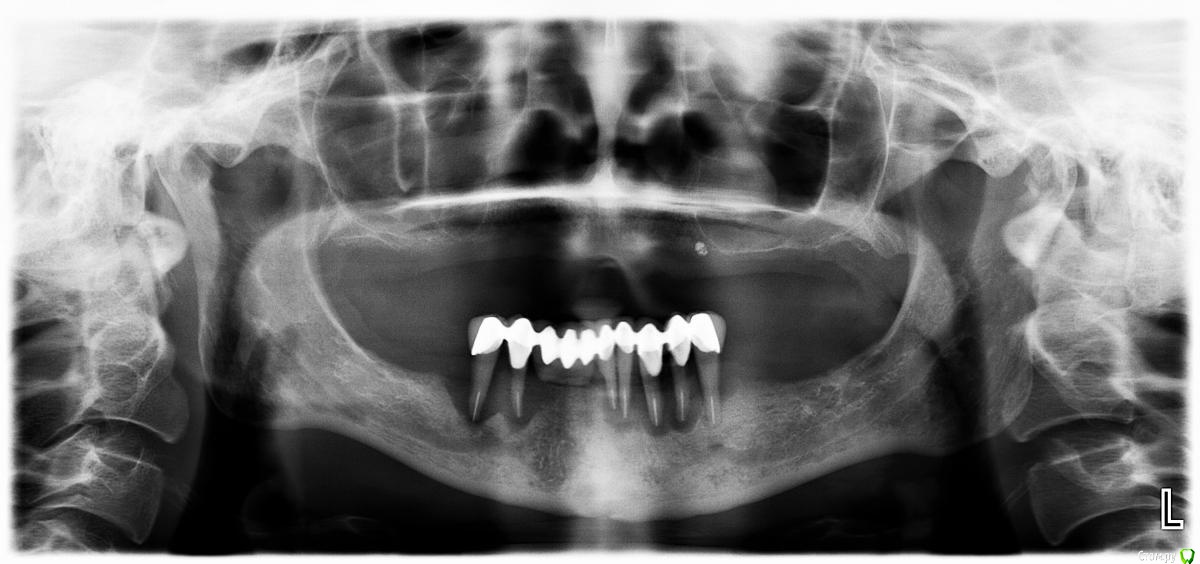

fly_R Опубликовано 15 января, 2017 Поделиться Опубликовано 15 января, 2017 Уважаемые специалисты! почти год изучала сайты по стоматологии, покрывалась мурашками, бросала опять читала и вот теперь понимаю, что ничего не понимаю...нужна помощь!!Схематично: 1. ВЧ- адентия полная - битва проиграна - полностью съемный протез 2. НЧ - подвижность зубов (остатков) нарастает , светит опять съемный протез ?? Мне только 50 будет.ЧТО ДЕЛАТЬ??? Все под снос; 1. Возможна ли имплантация сразу после удаления с немедленной нагрузкой, по типу all 4-6 с балкой ? или на винтики ? а в чем различие ??? обе конструкции очень коротенькие , вынос концов протеза создает плечо . вообщем качельки вырвут импланты на раз-два. больше имплантов -8 ? с костной пластикой, и что на время вростания -опять же съемный протез, как же работать?? можно конечно все крепить на" корегу" это уже мой регулярный завтрак . Да и ещё: я диабетик 1 тип на инсулине, кто же за меня возьмется ?? на стоме это даже озвучивать нельзя !!! шовинизм какой-то, а я ведь даже ребетёнка выносила и родила на инсулине !! Очень хочу услышать совет от "Зеленый"- ого, кажется он один отважился на импланты диабетикам. Как результат, есть ли надежда?? Ссылка на комментарий

Bier Опубликовано 15 января, 2017 Поделиться Опубликовано 15 января, 2017 надежда есть конечно. Надо смотреть КТ, наверху пройдет классическое all-on-four или 2 зигомы + 2 имплантата. Внизу тоже можно что-то придумать. 1 Ссылка на комментарий

Большой Зеленый Опубликовано 19 января, 2017 Поделиться Опубликовано 19 января, 2017 Ничего сверхсложного. Все решаемо.Надо КТ. Если за сахаром следить и держать не выше чем 10 ммоль/л то все работает.К гигиене конечно вопрос совсем другой.. Верх все на 4 . Низ я бы сделал в два этапа. Сначала удаление и Нкр ,потом имплантанты. Ссылка на комментарий